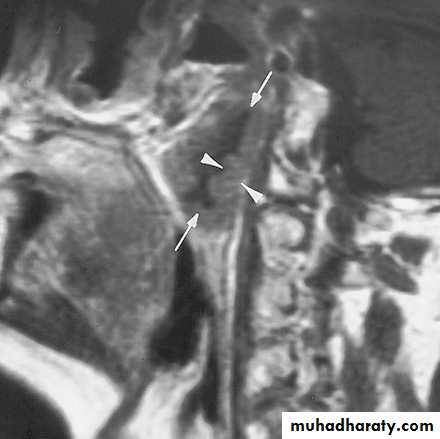

Magnetic Resonance Imaging

Similar information as CT

Better for upper neck and skull base

Vascular delineation with infusion

16

17